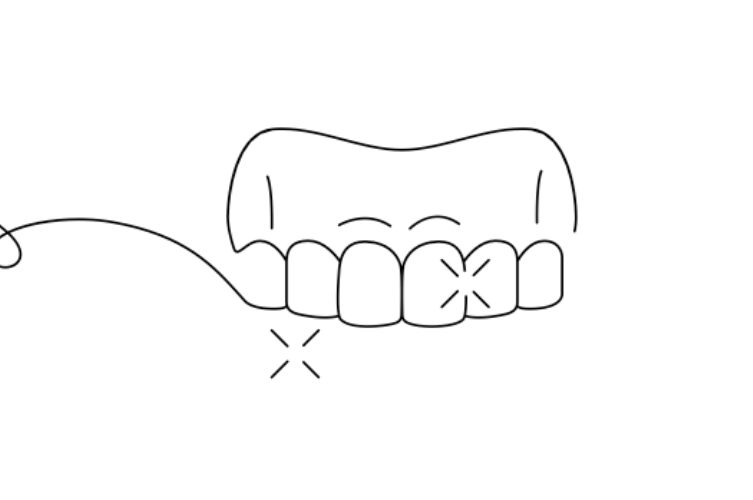

CONTENTION AMOVIBLE (GOUTTIERES DE MAINTIEN)

Similaires aux aligneurs transparents, elles sont portées principalement la nuit. Elles maintiennent les dents dans la bonne position et sont faciles à nettoyer.